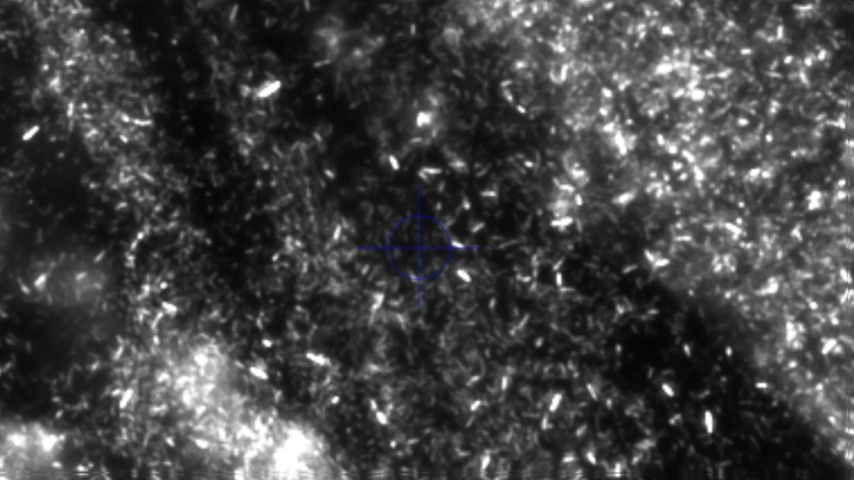

In Gegenwart von Urease produzierenden Bakterien wird Harnstoff im Urin zu Ammoniak und Kohlendioxid gespalten. Durch die Ammoniak- und CO2-Produktion und die darauffolgende Reaktion von CO2 mit H2O, die zu hohen Bicarbonatwerten führt, steigt der Urin-pH-Wert stetig an und pendelt sich schließlich bei 7,2–8,0 ein. Ammoniak wird dabei weiter hydrolysiert und bildet Ammoniumionen. Die basische Übersättigung des Urins führt bereits ab Urin-pH-Werten von 6,8 zu einer erhöhten Kristallisationsneigung von Kalziumphosphat zu Carbonatapatit. Zusätzlich kristallisiert im basisch übersättigten Urin ab einem Urin-pH-Wert >7,2 das basisch nur schwer lösliche Magnesium mit den Ammoniumionen zu Magnesiumammoniumphosphat (Struvit). Es bildet sich „Struvit-Apatit-Staub“ um die Urease produzierenden Bakterien. Sowohl in diesen Bakterien als auch in ihrer Umgebung kann es zur Kristallisation kommen. Die in den Bakterien gebildeten Mikrolithen können nach der Bakteriolyse den Grundstein für die Bildung von neuen Infektsteinen legen (Abb. 1 und 2).2,5

Abb. 2: Mikroskopische Darstellung von Fluoreszenz-markiertem Proteus mirabilis in und um den Struvitkristall nach Anzüchtung in artifiziellem Urin. Quelle: eigene Forschungsarbeit